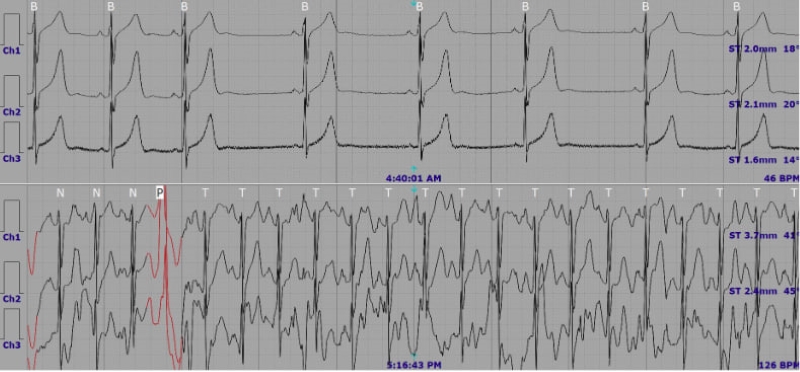

Trên bản ghi điện tâm đồ, bạn sẽ thấy những đường sóng lặp lại theo chu kỳ. Mỗi phần trong bản ghi đó mang ý nghĩa biểu thị riêng cho một giai đoạn hoạt động của tim:

- Sóng P: biểu thị quá trình co của tâm nhĩ.

- Phức bộ QRS: biểu thị cho quá trình co của tâm thất, phần này thường cao và nhọn.

- Sóng T: thể hiện quá trình nghỉ của tâm thất.

Nhịp tim đều khi các khoảng RR bằng nhau. Nhịp tim không đều khi khoảng cách giữa các sóng R thay đổi. Đây có thể là dấu hiệu của rối loạn nhịp tim.

3.4. Quan sát sóng T và đoạn ST

Sóng T biểu thị cho quá trình tái cực tâm thất. Bình thường, sóng T cùng chiều với phức bộ QRS. Nếu T đảo ngược hoặc quá cao có thể cảnh báo thiếu máu cục bộ, điện giải bất thường hoặc tác dụng phụ của thuốc.

Đoạn ST nên nằm trên cùng đường đẳng điện với đoạn PR. Nếu ST chênh lên hoặc xuống có thể phản ánh thiếu máu cơ tim hoặc nhồi máu cơ tim.